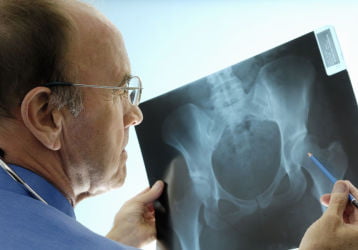

Рентгенография ТБС: особенности проведения, диагностические возможности и расшифровка

Как проводится рентген ТБС. В чем принцип лучевой диагностики. Расшифровка диагноза. Примеры снимков с разными диагнозами.